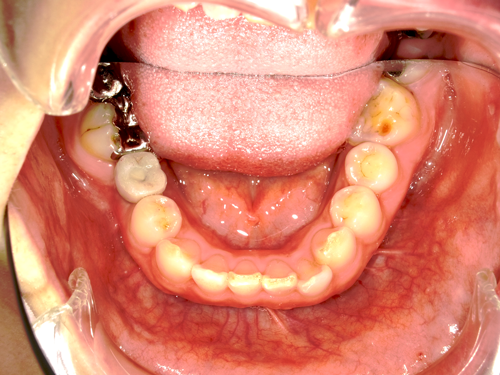

インプラントは、失われた歯の代わりに人工歯根(チタン製のインプラント体)を埋め込み、それを土台に人工の歯を固定する治療です。

人工の歯を顎の骨に直接固定するため、まるで自分の歯のように自然に感じられます。

インプラントは入れ歯のようにずれたり、もたついたりということがありません。

独立した歯を作るため、健康な歯を削ることや、バネをかけ負担をかけたりすることはありません。

インプラントは、審美性の高い素材を使用でき、自然な仕上がりを実現可能です。ほり歯科・矯正歯科中央林間では、精密性の高い治療により、より美しい仕上がりを目指しています。